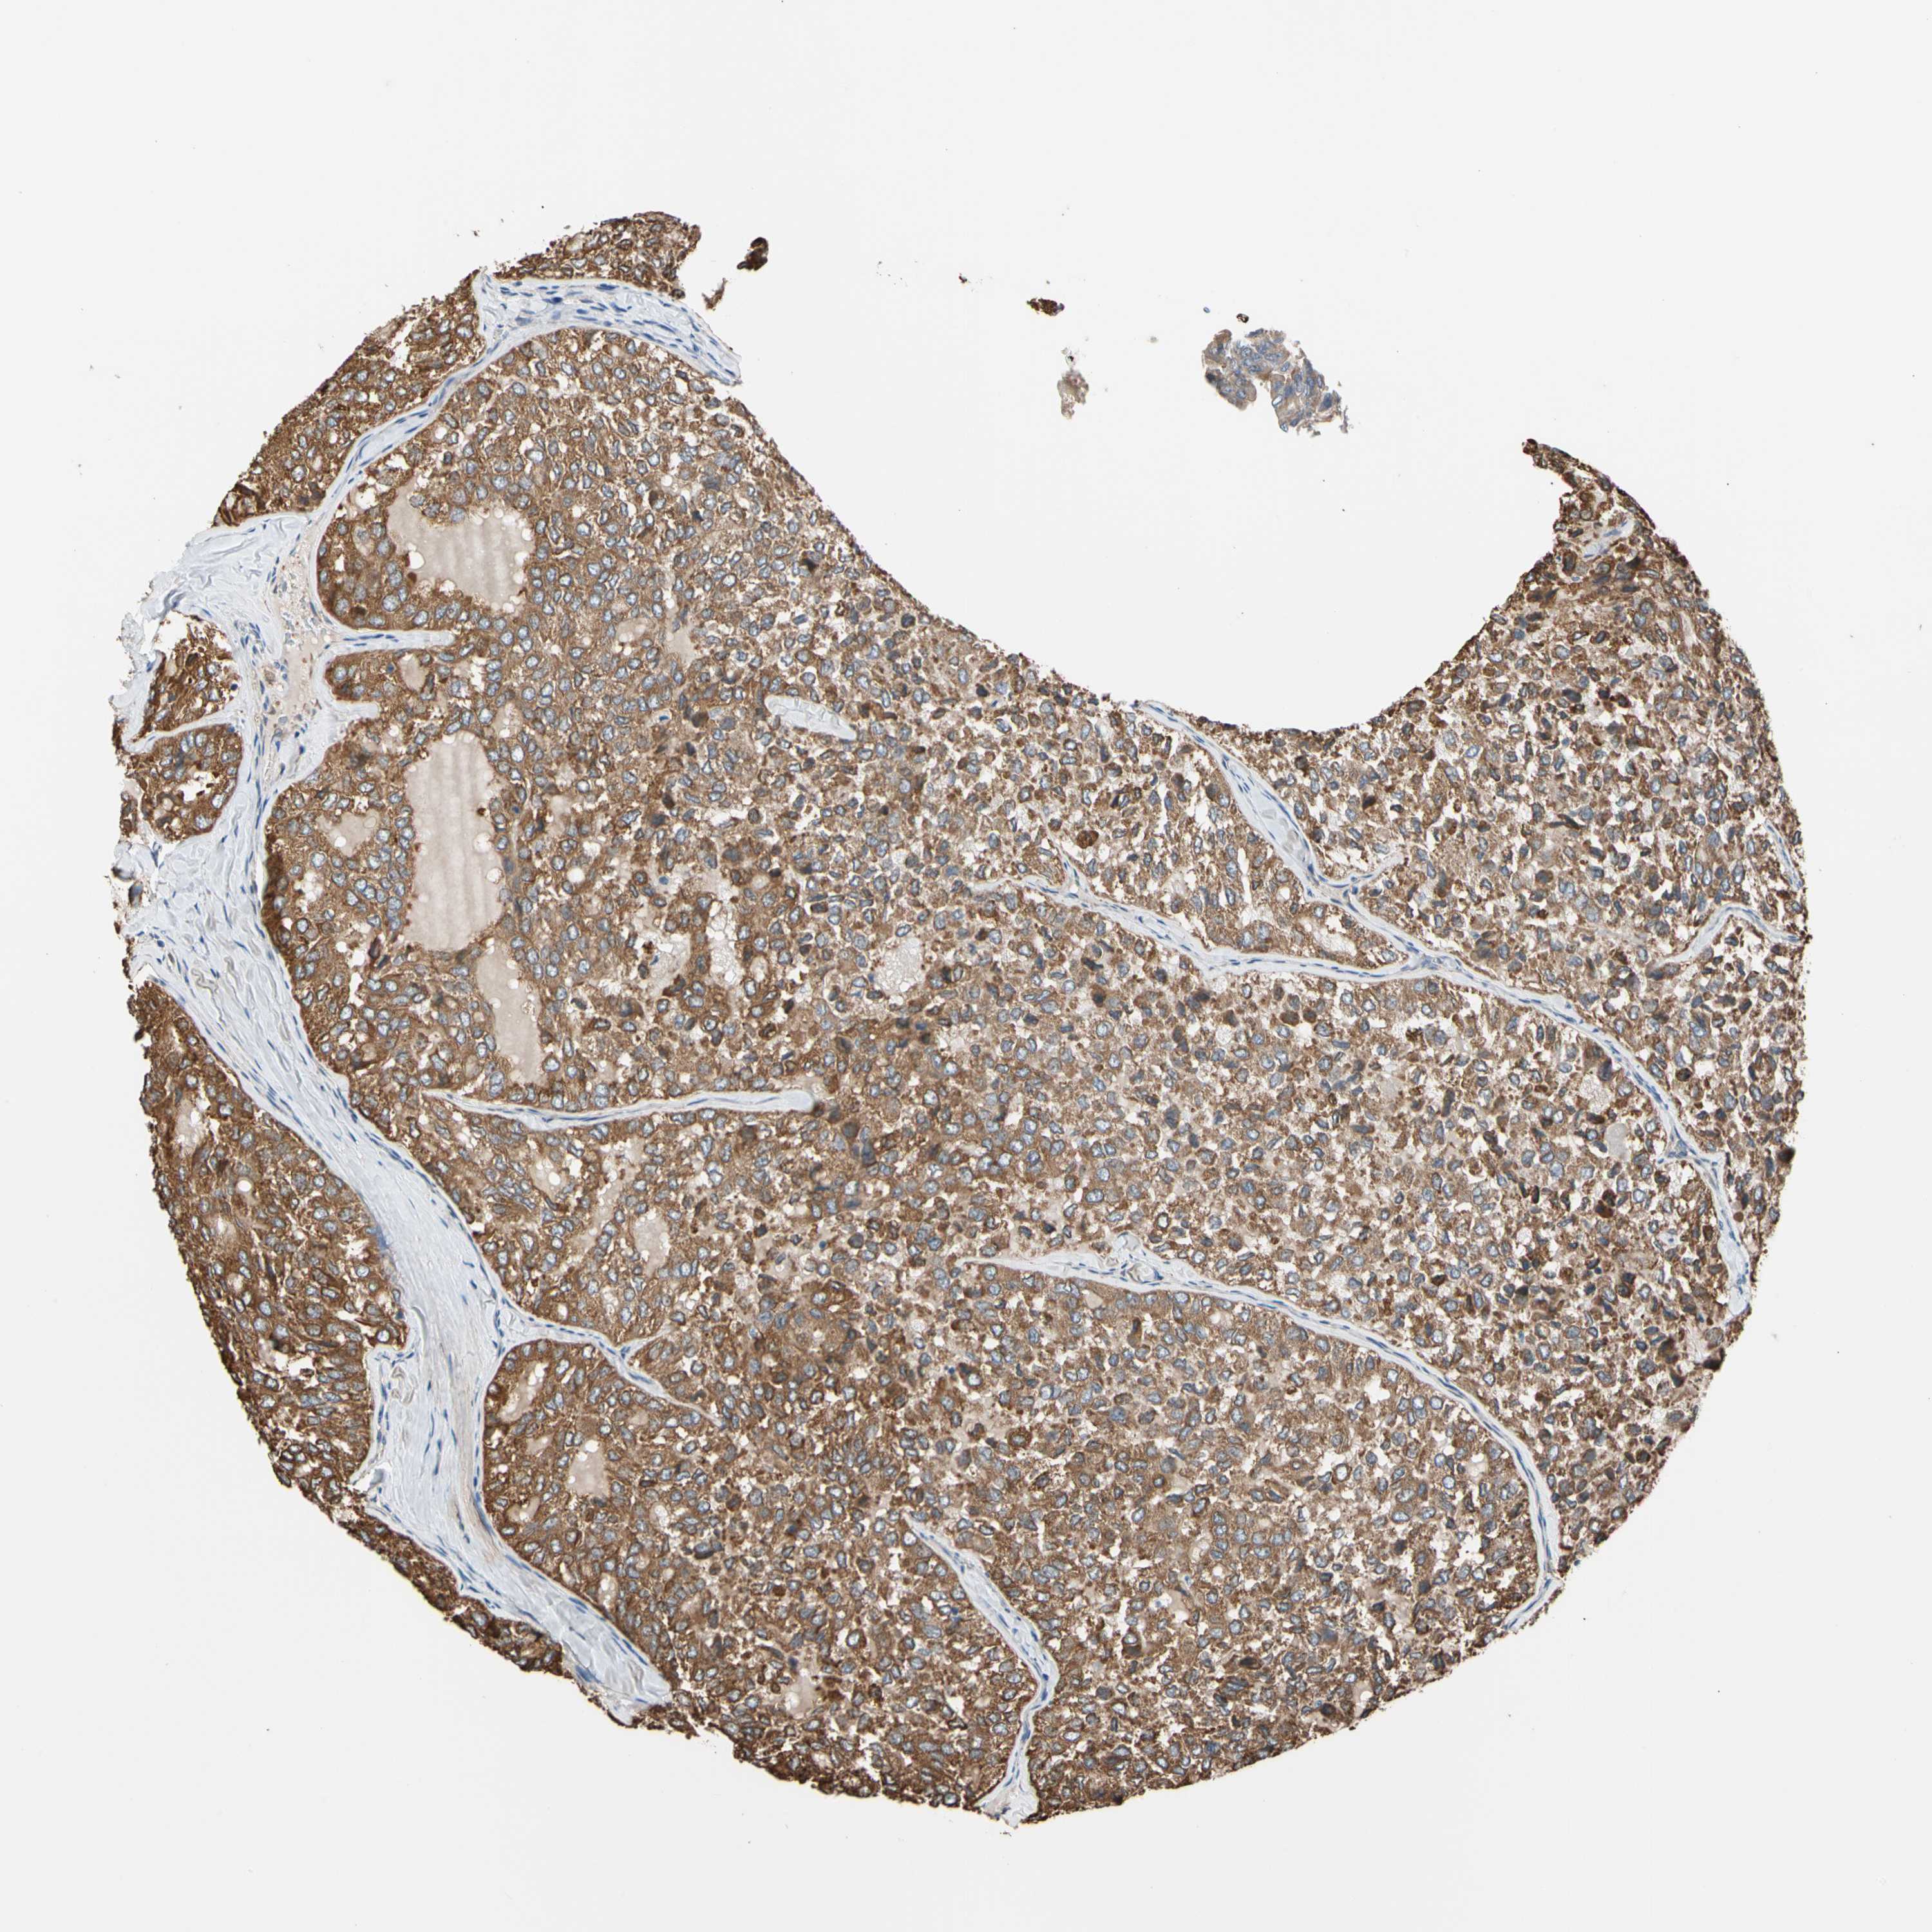

THYROID CANCER - Protein expressioni

A mouse-over function shows sample information and annotation data. Click on an image to view it in a full screen mode. Samples can be filtered based on level of antibody staining by selecting one or several of the following categories: high, medium, low and not detected. The assay and annotation is described here.

Note that samples used for immunohistochemistry by the Human Protein Atlas do not correspond to samples in the TCGA dataset.

Antibody stainingi

Antibody staining in the annotated cell types in the current human tissue is reported as not detected, low, medium, or high, based on conventional immunohistochemistry profiling in selected tissues. This score is based on the combination of the staining intensity and fraction of stained cells.

Each image is clickable and will lead to virtual microscopy that enables deeper exploration of all samples and also displays staining intensity scores, fraction scores and subcellular localization as well as patient and tissue information for each sample.

Antibody HPA008183

Antibody HPA053882

Antibody CAB019313

Staining

High

Medium

Low

Not detected

Intensity

Strong

Moderate

Weak

Negative

Quantity

>75%

75%-25%

<25%

None

Location

Nuclear

Cytoplasmic/membranous

Cytoplasmic/membranous,nuclear

Papillary adenocarcinoma, NOS

Follicular adenoma carcinoma, NOS